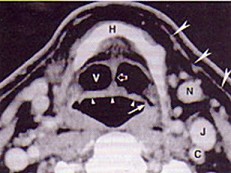

| 男,55岁,声嘶6年,有长期吸烟史。检查:无呼吸困难。喉镜检查:声带慢性充血,可见右侧声带可见菜花样新生物,右侧声带活动固定,喉部CT检查如下图: |

6.诊断首先考虑 ( )![]() ![]() ![]() ![]() |